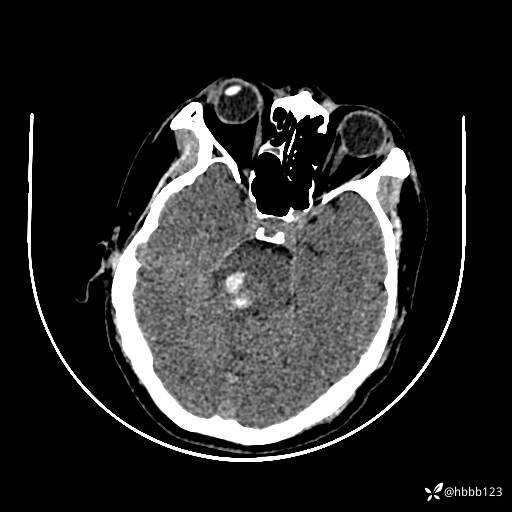

患者男,51岁。

简要病史:患者自述于1周前至某人民医院发现脑干肿瘤(具体不详),为求进一步诊断至我院就诊。

完善颅脑MRI平扫+增强,颅脑CT平扫:

颅脑CT平扫: